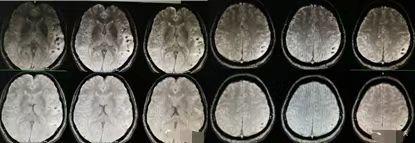

遂就诊于我院急诊,复查头颅CT:左颞叶梗塞灶伴局部出血灶不排除,左额叶、右侧脑室三角区旁及左侧小脑半球陈旧性梗死灶可能(图2)。

图2既往史:患者近1年内出现过4次发作性症状,有3次表现为出门后找不着回家的路,刚放的东西找不到,1次为偏执地要某物,拿到后又忘记放到哪,4次均未诊治,自行缓解。否认高血压、糖尿病、冠心病病史。